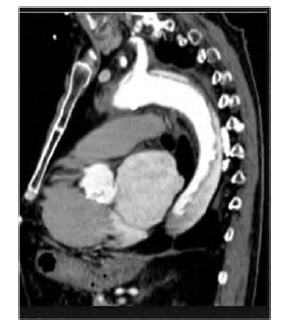

Um paciente hipertenso de longa data apresenta importante dor torácica, súbita, em facada, que iniciou há duas horas. Apresenta-se na emergência com PA de 200 mmHg X 120 mmHg e FC de 100 bpm. É realizada uma angiotomografia de tórax, exibida na imagem.

Com base nesse caso clínico, assinale a alternativa que apresenta a classificação e a conduta a se rem realizadas, respectivamente.